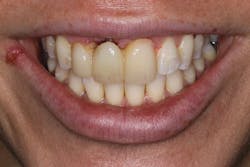

• site development to increase hard and soft tissue for pontic sites in fixed bridge prosthetics (figures 9–14);• correcting bone defects impinging upon anatomical structures after tooth extraction, such as oroantral communication (figure 18); and